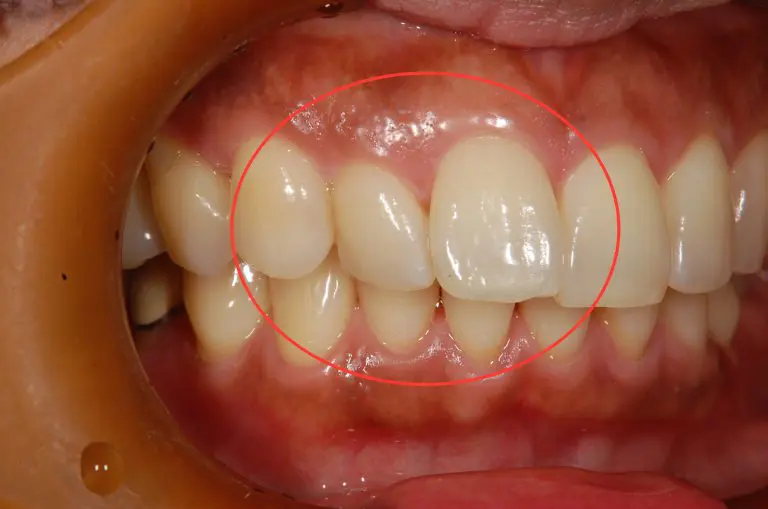

本症例の患者様は、右側前歯のずれを改善したいとのことで来院されました。

画像で右側前歯の一本が口唇側に、もう一本が舌側にずれているのが確認できます。

マウスピースを用いて、矯正を実施することとなりました。